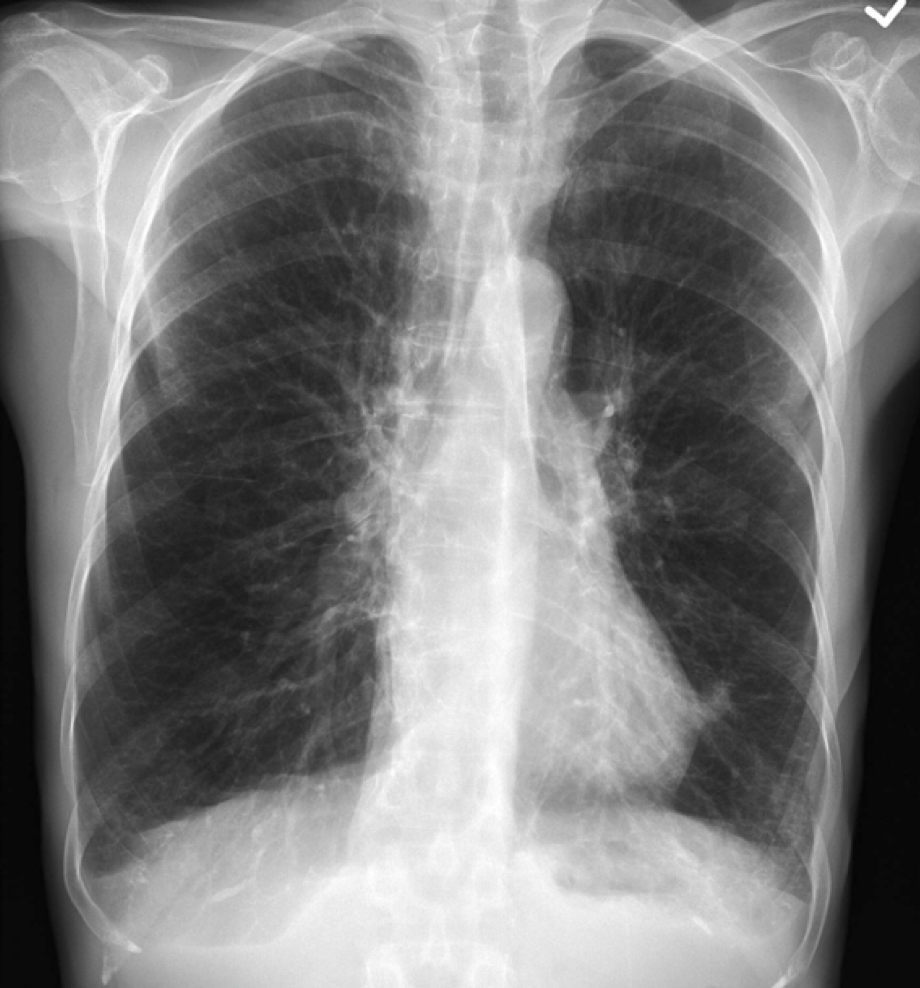

Which findings would you expect on a CXR from a COPD patient?